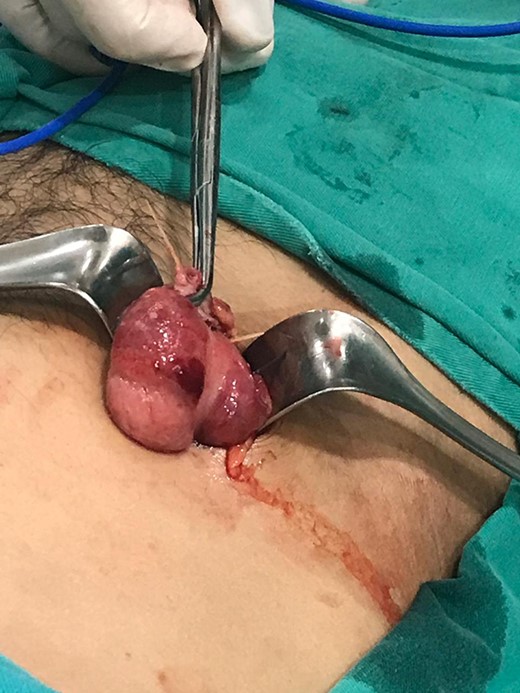

Intravenous antibiotics were commenced preoperatively and a Mcburney incision was made, multiple adhesions were found near the cecum, and the cecum wall appeared hyperemic with intense inflammation near the base of the appendix. After blunt dissection, two 3 cm toothpicks were discovered, one that perforated the appendix wall near its base and another one that jeopardized the cecum wall (Figs 1–3).

Hyperemic cecum wall with intense inflammation near the base of the appendix.

Transoperative image of the cecum and appendix with the two toothpicks.